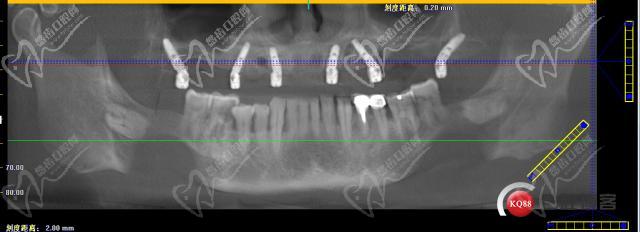

all-on-6種植牙種植體在口腔內(nèi)的植入牙片